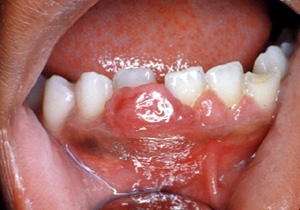

Este ejemplo

es bastante vascular. Ha cambiado de sitio al incisivo central hacia

lingual. Los granulomas decelulas

gigantes tienen un mayor potencial de crecimientoque el granulomas periférico y puede cambiar de lugar los

dientes.

Aquí hay un

ejemplo típico de un granuloma de celulas gigantes; sin embargo, sólo por

la biopsiaescisionales posible el diagnóstico.